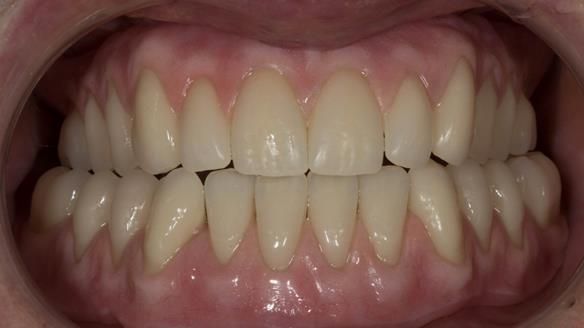

This newsletter describes in step by step detail the provision of a lower implant supported metal based complete denture with three dental implants positioned in the anterior mandible. The upper arch was restored with a metal based complete upper denture.

"An improvment in appearance would also be appreciated."

- Bland aesthetics.

I provided new metal based complete dentures. The clinical situation and treatment process is shown in detail below with photographs. I provided the clinical work and Rowan Garstang provided the technical work. The dentures took 5 visits to make - with the patient travelling by plane from Ireland to Manchester. The patient had one review after the dentures were fitting.